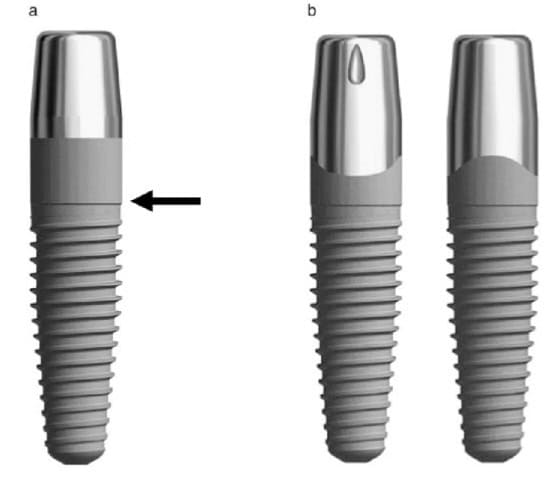

Likewise, the attempt to bring immediacy into the mainstream around 2004 proved to be a bridge too far. The commercial vehicle to materialise the promises of immediacy was soon launched and it was no other than implants designed for placement in extraction sockets aiming to receive immediate provisionals and promising to preserve tissue. Nobel Perfect and Nobel Direct, were two implants launched and marketed as the “immediacy” implants. They were one-piece implants with certain features that were expected to optimise outcomes of placement in fresh extraction sockets. Among these was the provision for a cement retained crown, the lack of an implant-abutment “gap” and also the coronal extension of rough surface, which was envisioned to enhance the attachment of the soft tissue. For this purpose and also to support interproximal papilla, Nobel Perfect had scalloped margins of the rough surface. The spatial positioning of an immediate implant at that time was also not perceived as today; there was a misguided view that filling the socket with titanium was the element which lead to bone preservation. This might be the principle behind another immediacy implant, around that time from Straumann, the TE implant which was a tissue level implant with characteristically wider coronal part.

immediacy implants

Nobel Direct (a) and Nobel Perfect (b) were only two of the many implant designs that were introduced for the purpose of immediate placement, about 20 years ago. Since then many designs have followed other are currently being introduced as we speak. As we now well know, not all designs were successful.